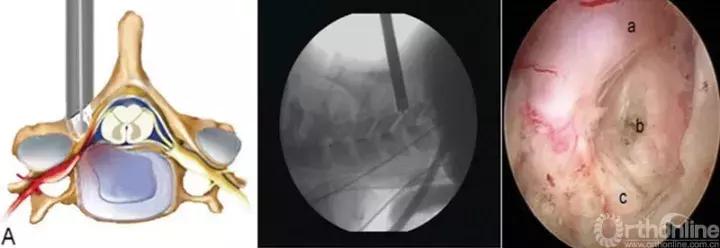

颈椎后路经椎间孔入路骨性标志点为“V”点,操作时注意“靶区触骨,动力先行,显根上下,脊髓勿碰。”也就是说,建立靶区应落到V点骨性结构部分,再用动力沿V点磨除外层皮质骨,黄韧带边缘会自然显露,再用Kerrison钳扩大显露神经根肩部与腋部,用神经勾进行探查和髓核摘除,手术全程都要注意保护脊髓,避免通过后方进行椎间隙髓核摘除这一危险操作。

颈椎前路:与腰椎相比,颈椎由于毗邻结构复杂,穿刺风险相对较高,尤其在前路进行经皮内镜手术时更为明显。鉴于在颈椎开展经皮内镜脊髓神经损伤“零容忍”,穿刺时应特别注意技巧,即“气管投影,两指技术,皮触骨面,侧透避深。”术中透视时需找到气管侧方投影位置,然后用中指和无名指将血管鞘和内脏鞘推挤开,直至皮肤触及骨面,在两指之间穿刺入椎间隙后需透视证实未进入椎管,以确保脊髓安全。